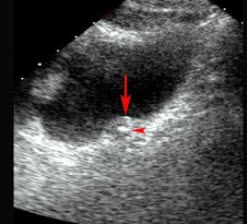

78、单项选择题

一患者,发热,右上腹痛,血常规检查白细胞增多。结合超声声像图,诊断为()

A.肝脓肿

B.肝血管瘤

C.肝癌

D.脂肪肝

E.肝囊肿